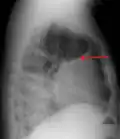

Op een longfoto is pleuravocht zichtbaar als een wit gedeelte op de longfoto.[4] Op een normale thorax foto is de ruimte tussen de viscerale pleura en de pariëtale pleura niet zichtbaar. Wanneer er pleuravocht aanwezig is, is deze ruimte wel zichtbaar. De densiteit van pleuravocht is ongeveer gelijk aan die van water, hierdoor is dit witter op een longfoto in vergelijking met de rest van de long (die meer de densiteit van lucht heeft). Door de hogere densiteit zal pleuravocht zich altijd bevinden op het laagste punt van de thoraxholte en is er een bij horizontale vloeistofspiegel (meniscus).[5] Een longfoto in zijligging (op de zijde waar het pleuravocht zich bevindt) is sensitiever voor pleuravocht. Dit wordt een "decubitus opname" genoemd, bij deze opname wordt een hoeveelheid van 50 ml of meer pleuravocht zichtbaar. Een CT-scan van de borstkas is het meest nauwkeurig voor het bepalen van de aanwezigheid van pleuravocht, maar ook de hoeveelheid en kenmerken van het pleuravocht. Ook echografie kan gebruikt worden om pleuravocht aan te tonen.[6]

Pleuravocht te zien op een laterale longfoto (een longfoto vanaf de zijkant).